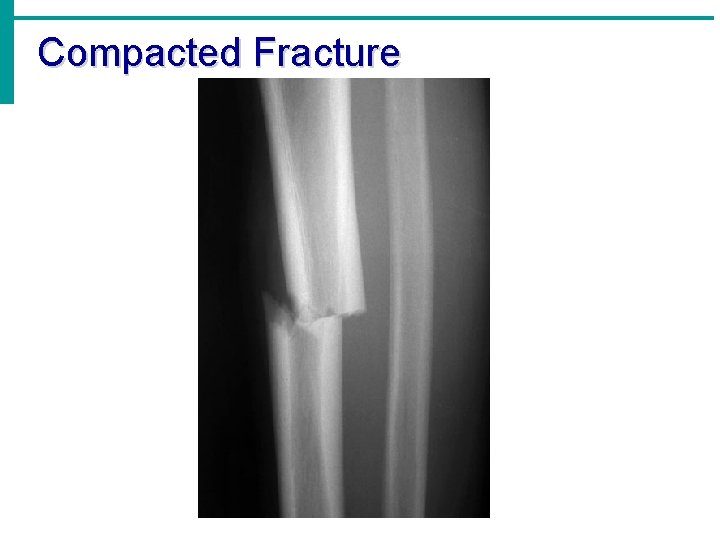

Compacted Fracture